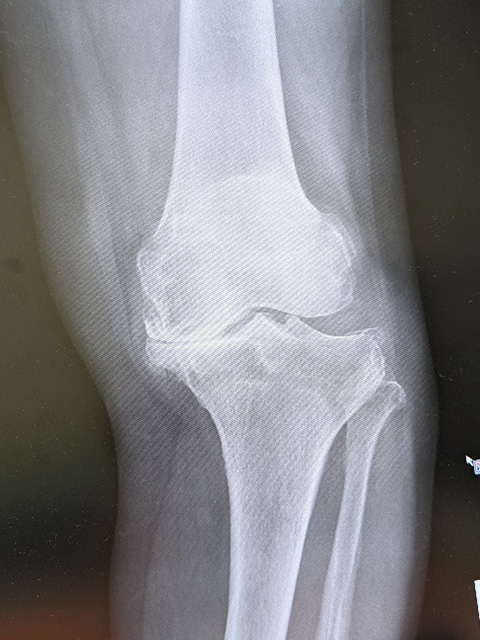

人工膝関節置換術

膝関節の軟骨のすり減りや骨の変形により歩行時の痛みが強い場合に行う手術で、膝の痛んでいる部分を切除し金属に置き替える手術です 痛みの軽減と歩行能力の改善には大きな効果があります 変形が進行し、強い痛みのため日常生活に支障が出ている方に適した治療法です。

高度な変形やリウマチなどに対しは全人工膝関節置換術(TKA)を行います。痛みが膝の内側か外側だけの場合には単顆部膝関節置換術(UKA)行います。